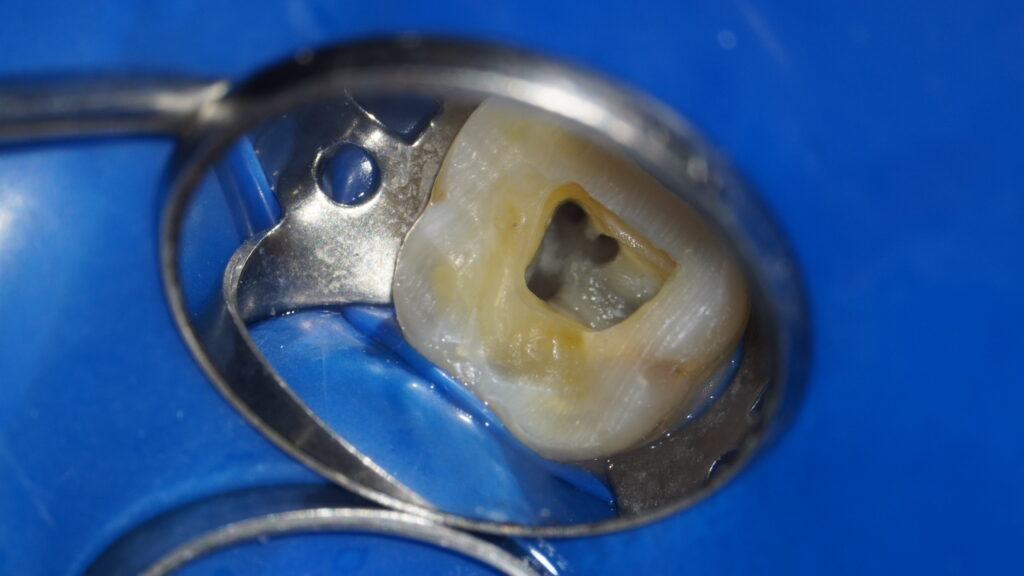

ラバーダム防湿とは、治療する歯以外を医療用のゴムシートで覆い、唾液や呼気に含まれる細菌の侵入を防ぐ治療法です。根管治療は無菌的な環境が大前提であり、細菌をいかに排除するかが成功のカギです。

当院では保険診療、自費診療を問わず、全ての根管治療にラバーダム防湿を徹底し、治療中の再感染を防止しています。